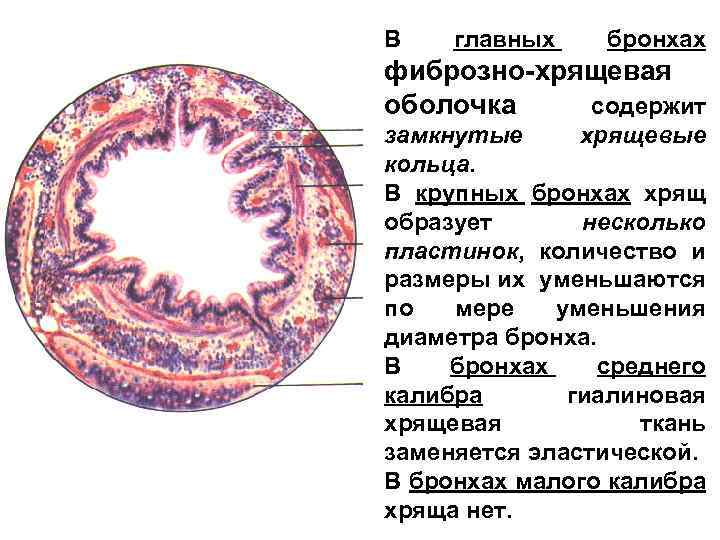

В главных бронхах фиброзно-хрящевая оболочка содержит замкнутые хрящевые кольца. В крупных бронхах хрящ образует несколько пластинок, количество и размеры их уменьшаются по мере уменьшения диаметра бронха. В бронхах среднего калибра гиалиновая хрящевая ткань заменяется эластической. В бронхах малого калибра хряща нет.